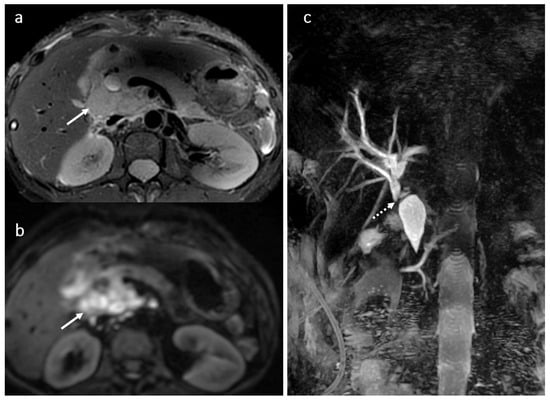

3.7. BT Lithiasis